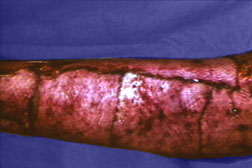

Tape is the least reactive of man-made wound closure materials. Tape with hypoallergenic adhesive on spun bonded nylon without reinforcing filaments has the best record for avoiding premature detachment. It also reduces the incidence of stress blister formation